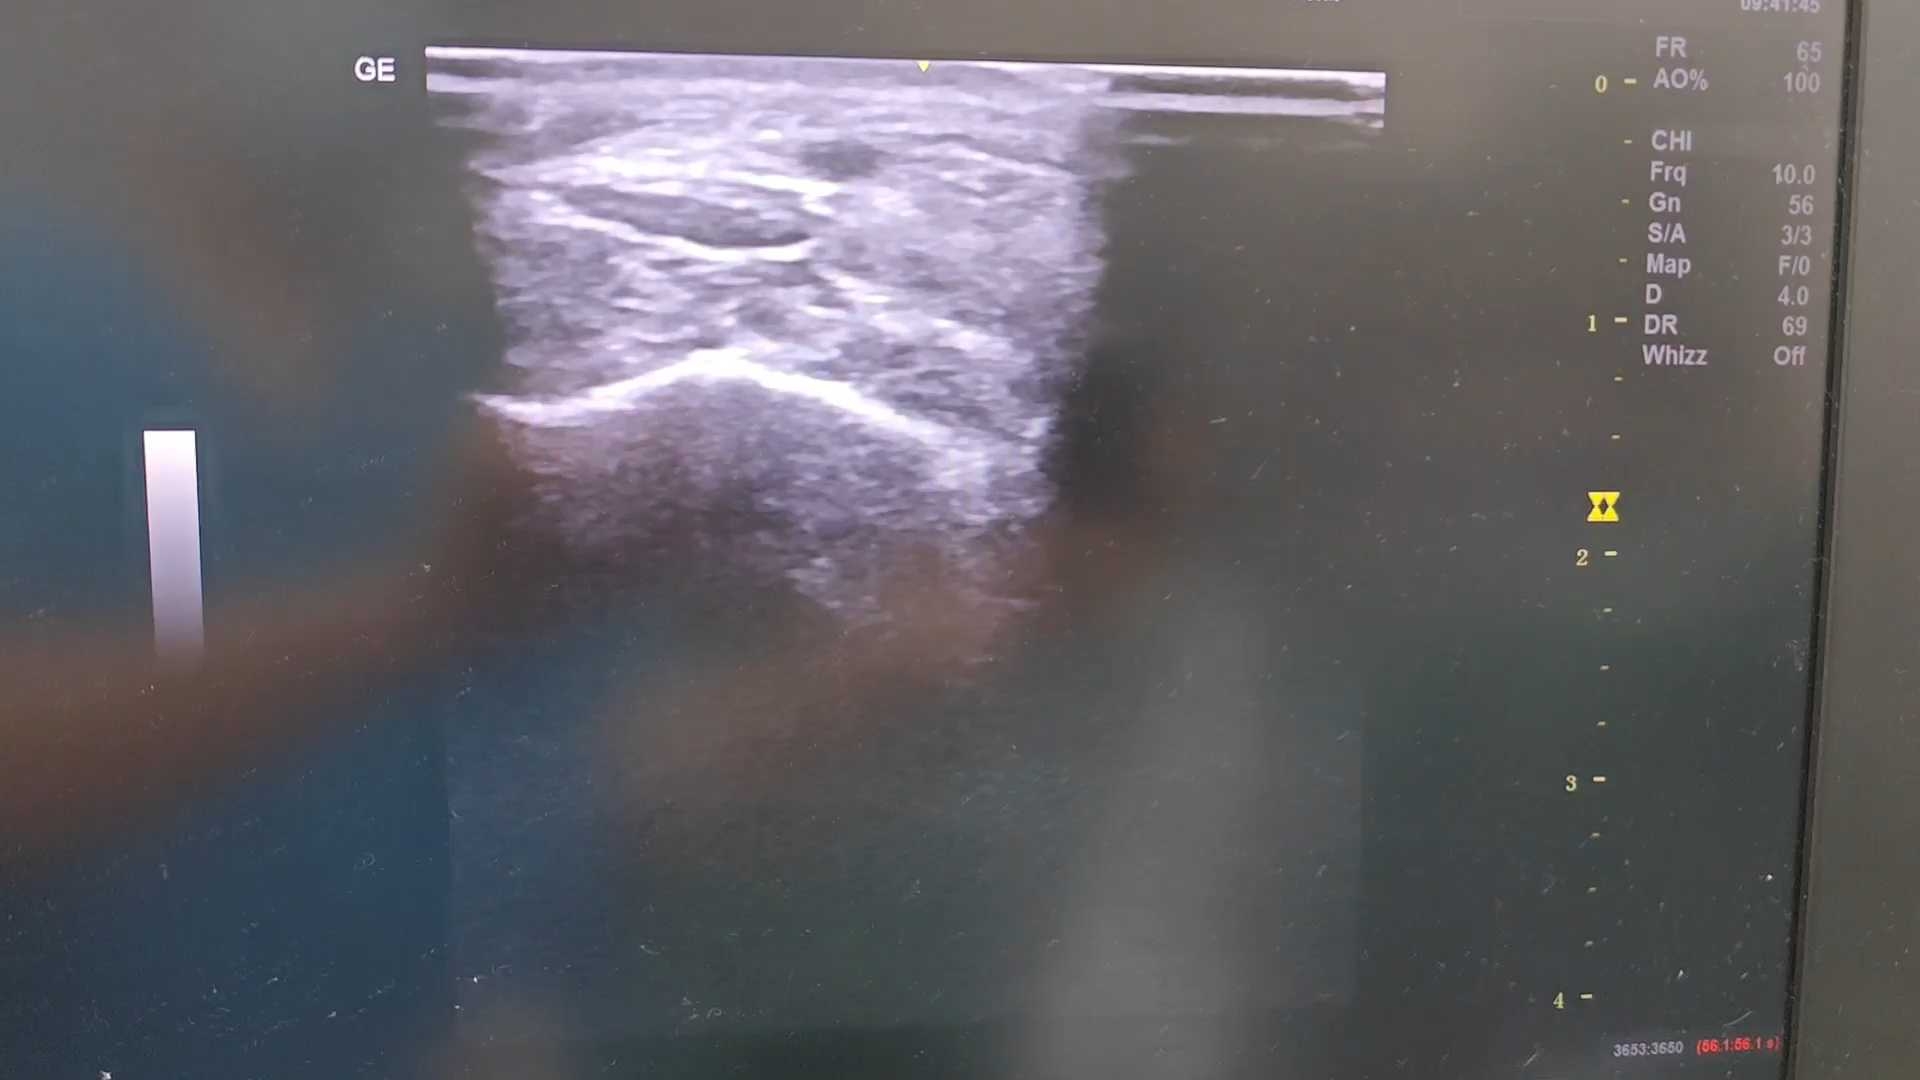

超声评估外踝可见少见的“人”字形穿通静脉